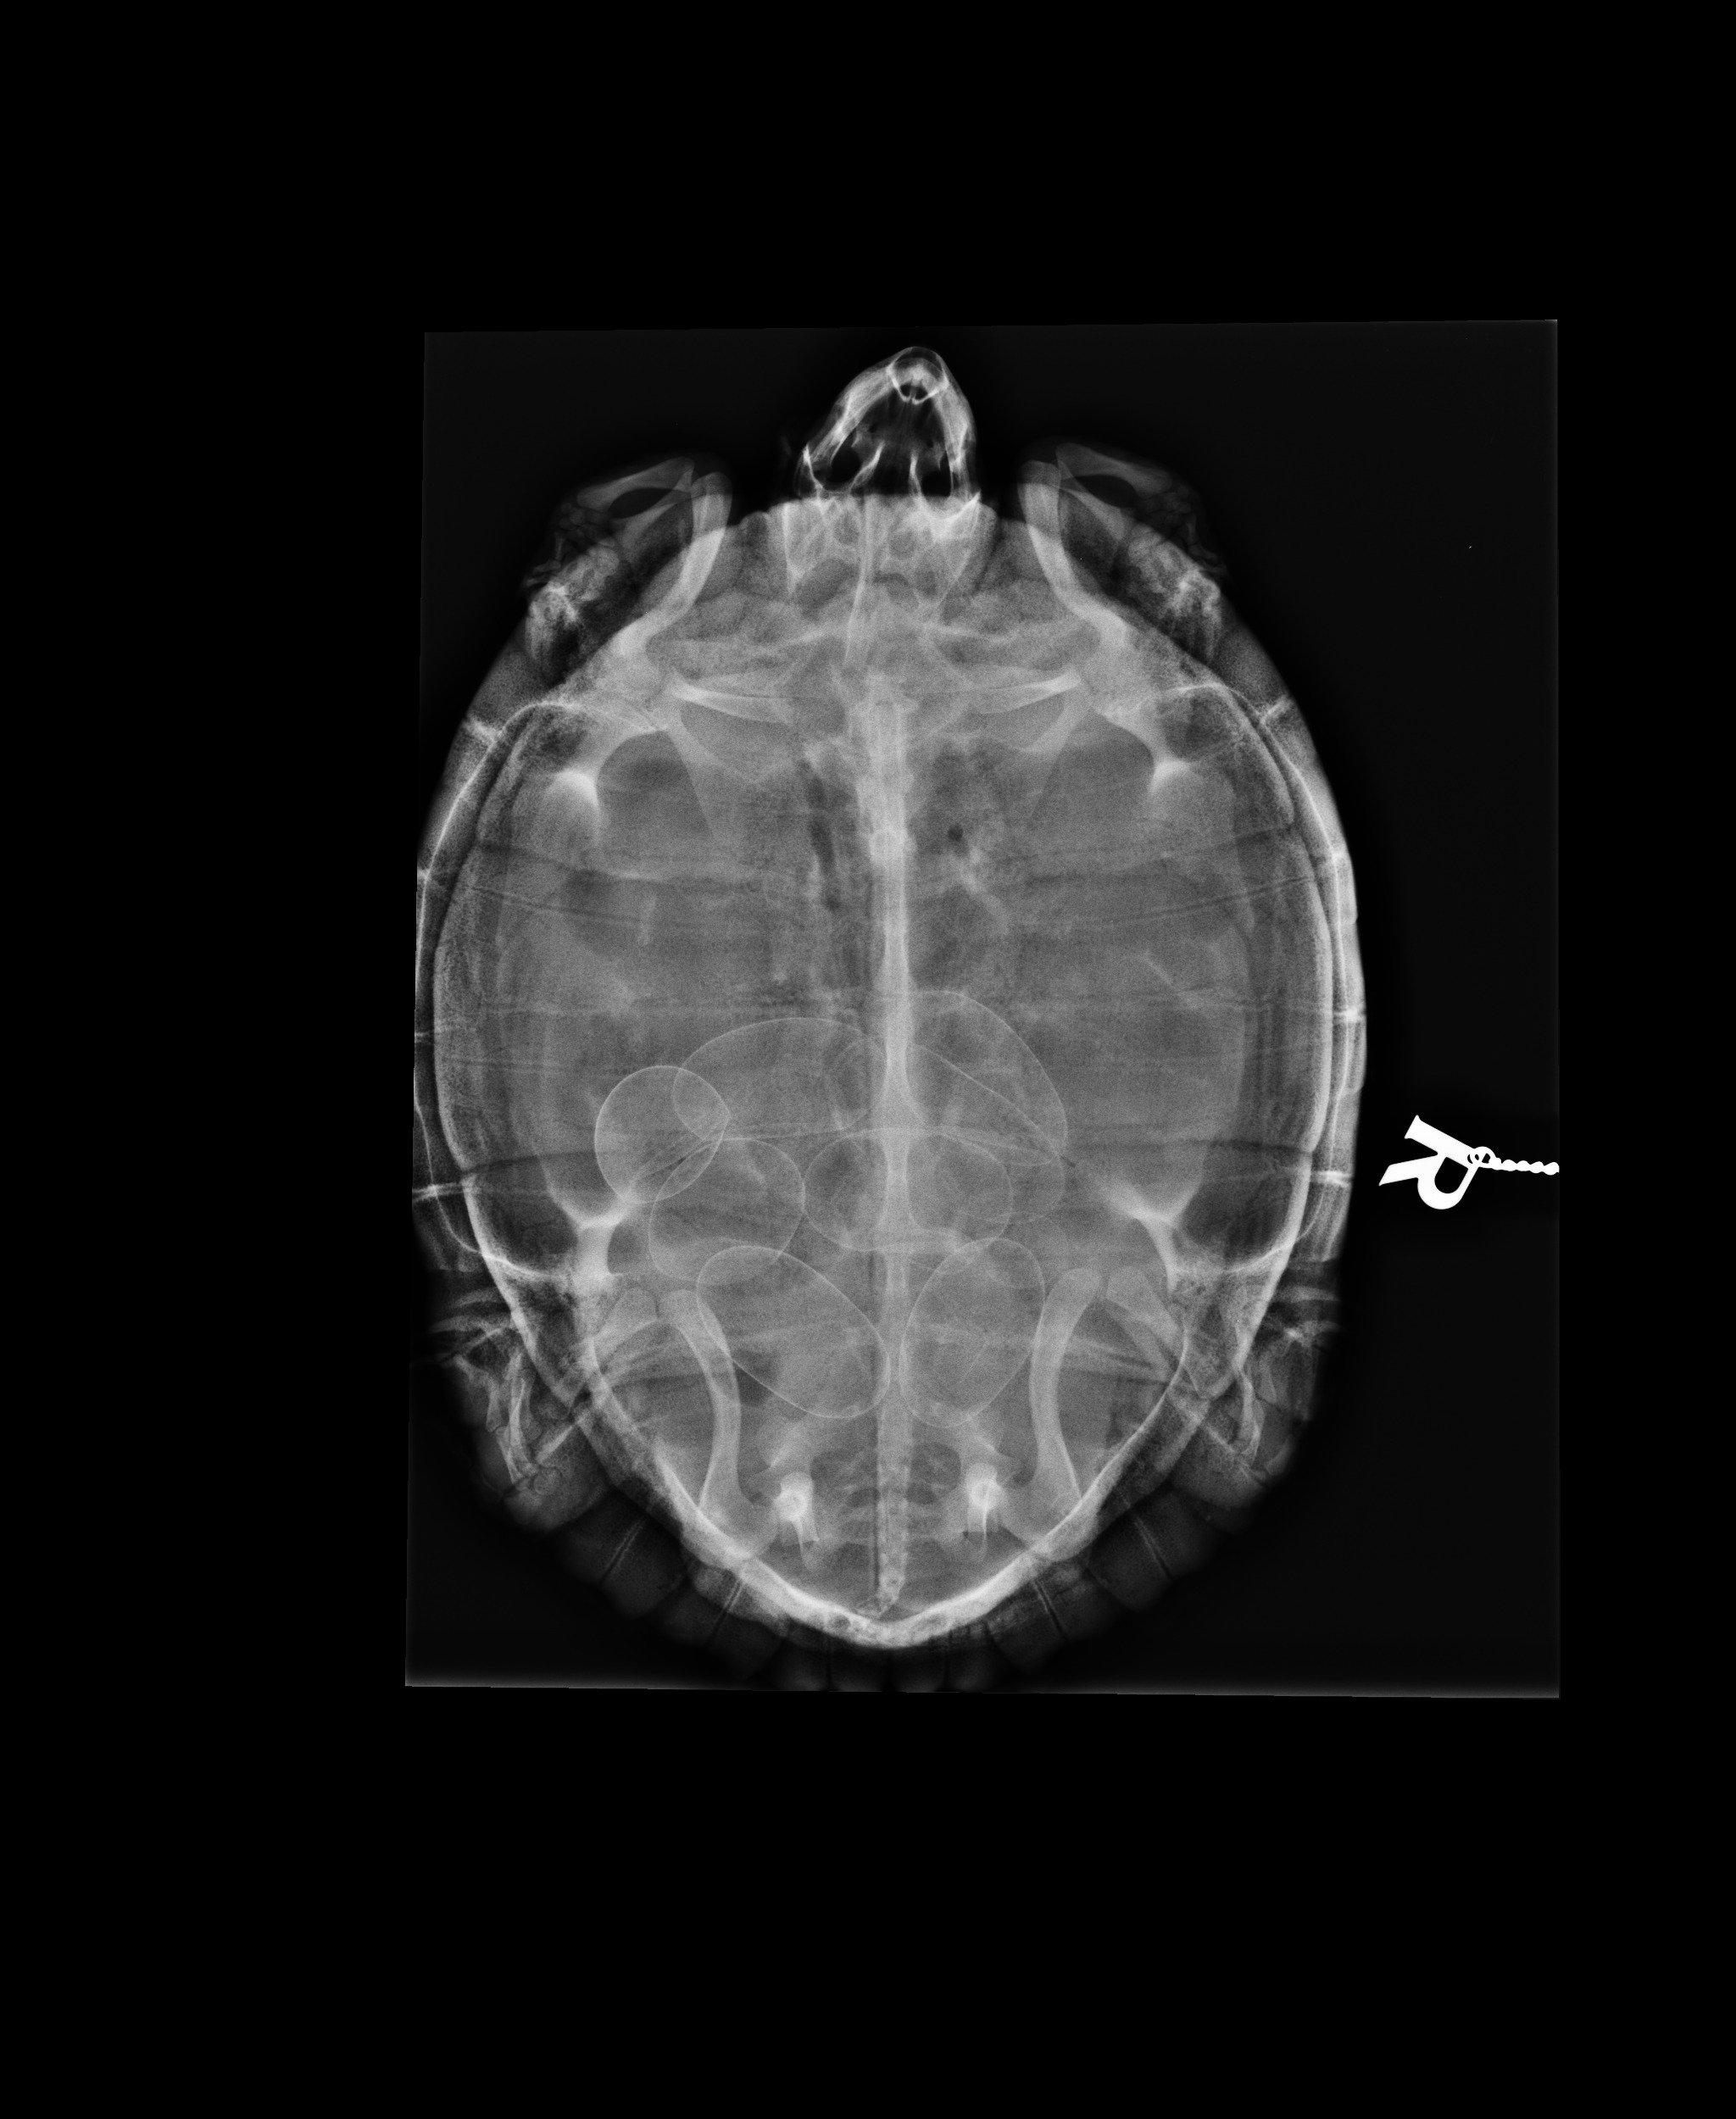

- Bildgebende Diagnostik